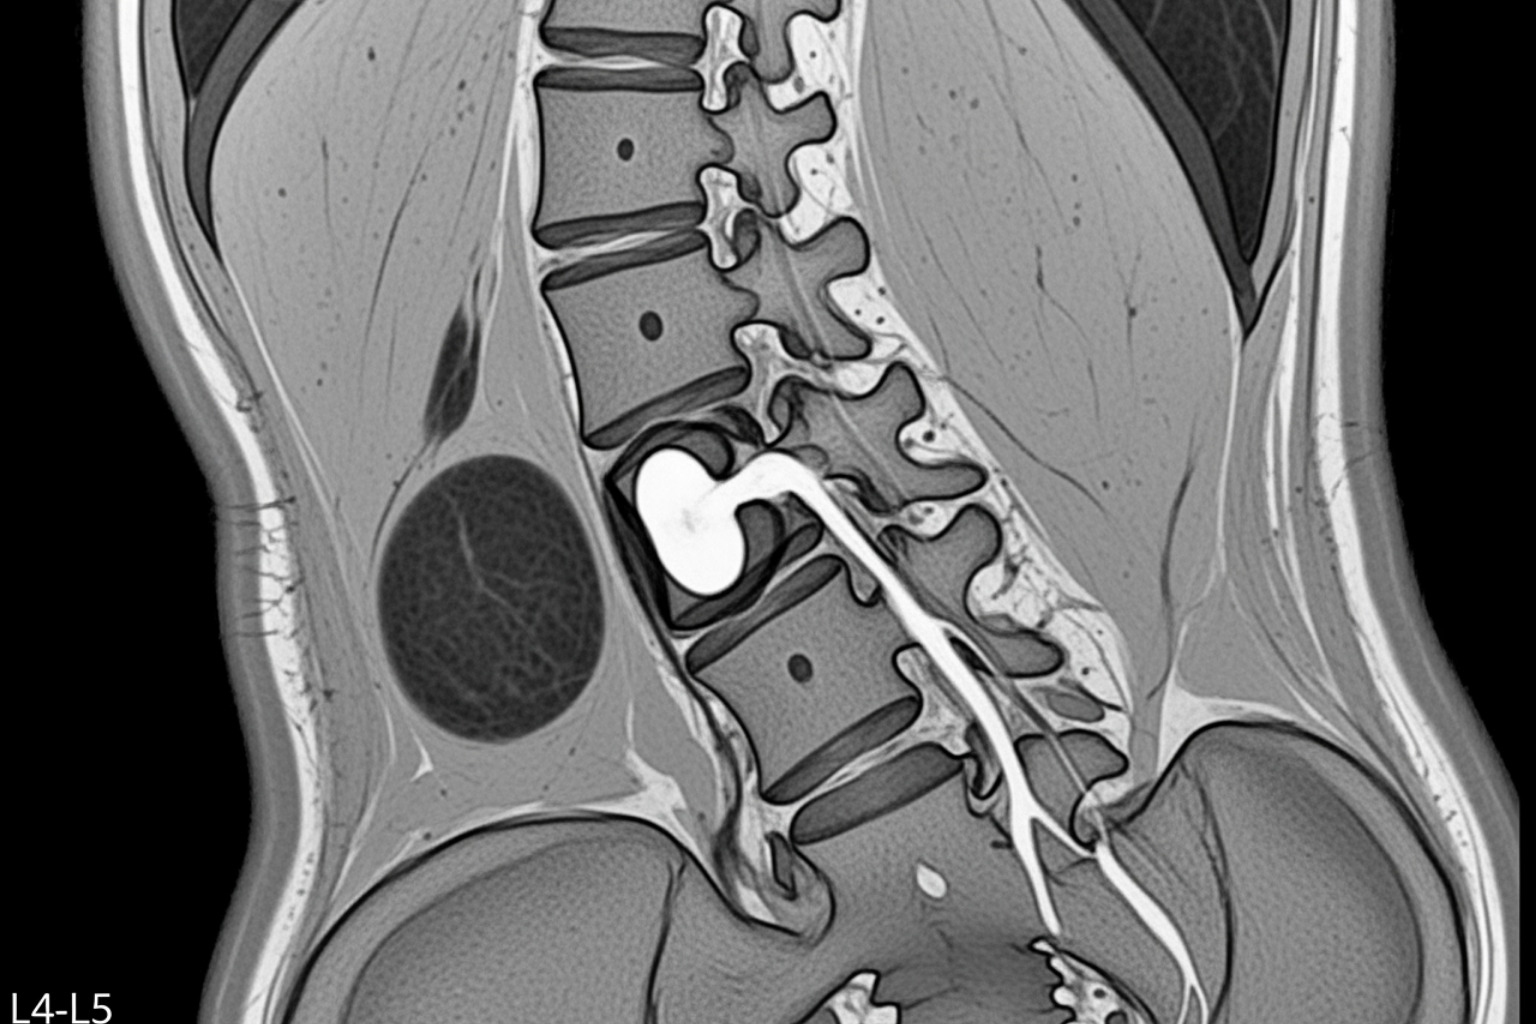

- MRI Scans: The best tool for visualizing soft tissues. An MRI can clearly show a herniated disc or spinal stenosis pressing on the nerve.

CT Scans: Excellent for visualizing bone structures, such as bone spurs or narrowing of the spinal canal.

X-rays: Used to spot bony issues like fractures, misalignments (spondylolisthesis), or significant bone spurs.